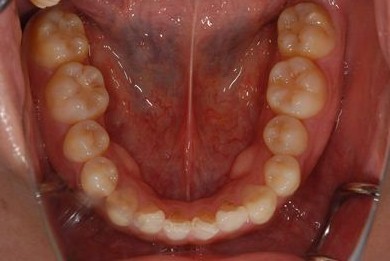

治療後

• 治療後